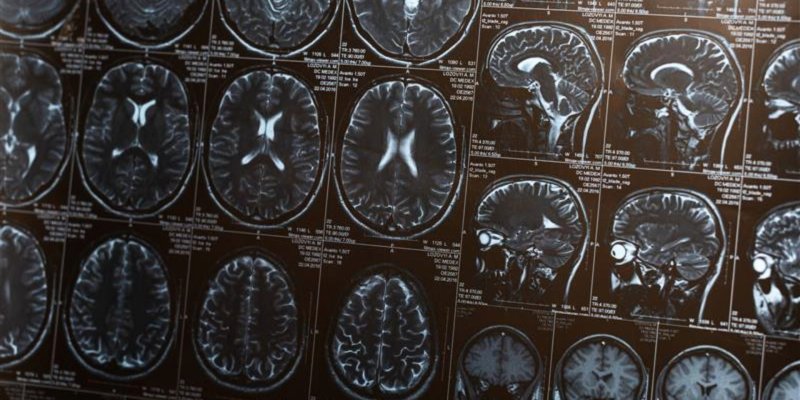

At any one time, more than 1000 clinical trials are being conducted across the Cambridge Biomedical Campus, the largest gathering of clinical, pharmaceutical and biomedical research specialists in Europe. These trials are a crucial step in the design of new medicines and medical devices – translating ideas that started in a research laboratory into new treatments for patients.

Cambridge is recognised as a leading centre for scientific translation and is chosen by many government and charity organisations to develop new medical treatments for a wide range of conditions, including obesity and diabetes, dementia, immune and inflammatory disorders, and cancer. The Clinical Research Centre, located adjacent to the world-leading Addenbrooke’s Hospital, provides the facilities to undertake Early Phase (I/II) human trials and translational studies, which help to advance research that may in future improve quality of life for millions.